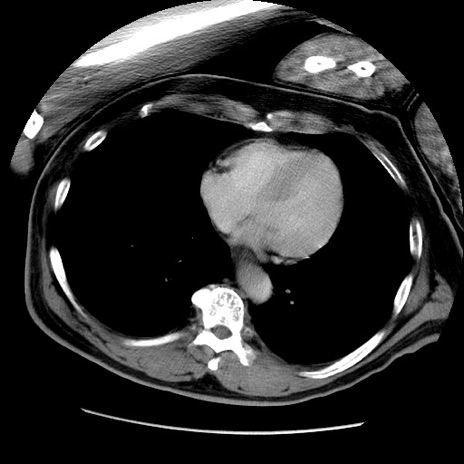

症例22(横断像)

【症例】50歳代男性

【主訴】腹痛

【現病歴】AVMからの被殻出血のため回復期リハ病棟入院中。 本日午後3時頃急に下腹部痛が出現した。

【既往歴】AVM、被殻出血、虫垂炎、高血圧

【身体所見】意識晴明、左半身不全麻痺、会話の理解は良好、36.5°C、腹部:膨隆、全体に板状硬、下腹部正中に圧痛点あり、反跳痛-、筋性防御不明、右下腹部にope scar

【データ】WBC 9400、CRP 0.06